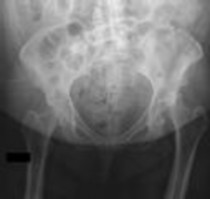

Question 4:

A 12-year-old obese male presents with left thigh pain and an antalgic gait for 4 weeks. He has been entirely unable to bear weight on the left leg for the past 2 days. Radiographs show a slipped capital femoral epiphysis (SCFE) with a slip angle of 60 degrees. What is the most significant risk factor for the development of avascular necrosis (AVN) in this patient?

Correct Answer: Inability to bear weight

Explanation:

The clinical inability to bear weight, even with crutches, defines an unstable SCFE according to the Loder classification. Unstable SCFE carries a significantly higher risk of avascular necrosis (AVN), historically up to 50%, compared to stable SCFE where AVN is rare. While a severe slip angle increases the technical difficulty of fixation, stability is the primary predictor of AVN.